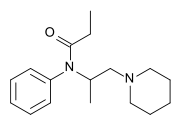

Anilidopiperidines